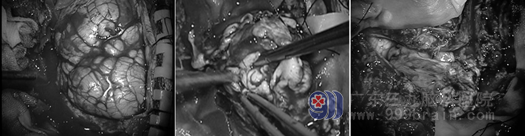

手术过程:剪开硬膜见肿瘤组织,质白,呈巨大脑回样改变,血管位于脑沟内,肿瘤血供丰富,充分减压,大部分切除。